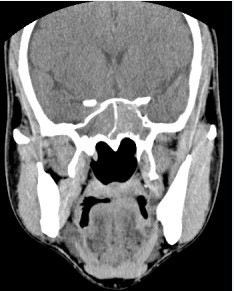

A 42-year-old man was referred to our hospital on 21 April 2005, complaining the 6 months right-side discontinuity nasal obstruction and 1 month right-side headache without pain of larynx, rhinorrhoea and epistaxia. On physical examinations,there was no new mass observed in the right-side nasal cavity. Computed tomography (CT) of the head and neck showed a mass localized to the sphenoid sinus cavity, but no bony destruction (Figure 1)

Figure 1: Computed tomography (CT) scan in the coronal view showing a mass localized to the sphenoid sinus cavity, but no bony destruction.